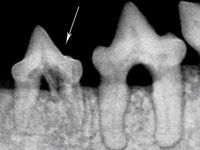

Photo 3: The left mandibular third premolar, tooth 307 (arrow), demonstrates both types of tooth resorption. The mesial root has a periodontal ligament space consistent with Type 1 tooth resorption. The distal root has an indistinguishable periodontal ligament space and resembles Type 2 resorption.

Grossly, Type 1 tooth resorption is characterized by gingivitis and periodontitis generally initiated at the junction between the cementum and the enamel. The origin is thought to be inflammatory. Cavitation defects are seen in the crown, with inflamed gingival tissue often covering the defect (Photo 1). Radiographically, these teeth have variations in density in the crown or root. A distinct periodontal ligament space is generally appreciated (Photo 2). Type 1 and Type 2 tooth resorption may be observed concurrently in individual roots of a single tooth (Photo 3). Therefore, diagnostic evaluation of each root is important to determine how each should be approached therapeutically.

Type 2 (Photos 2 and 3) tooth resorption is generally thought to start at the apical half of the root. Crown involvement is generally not noted until late in the resorption process. The hallmark of Type 2 resorption is the lack of radiographic evidence of a periodontal ligament space surrounding the root.